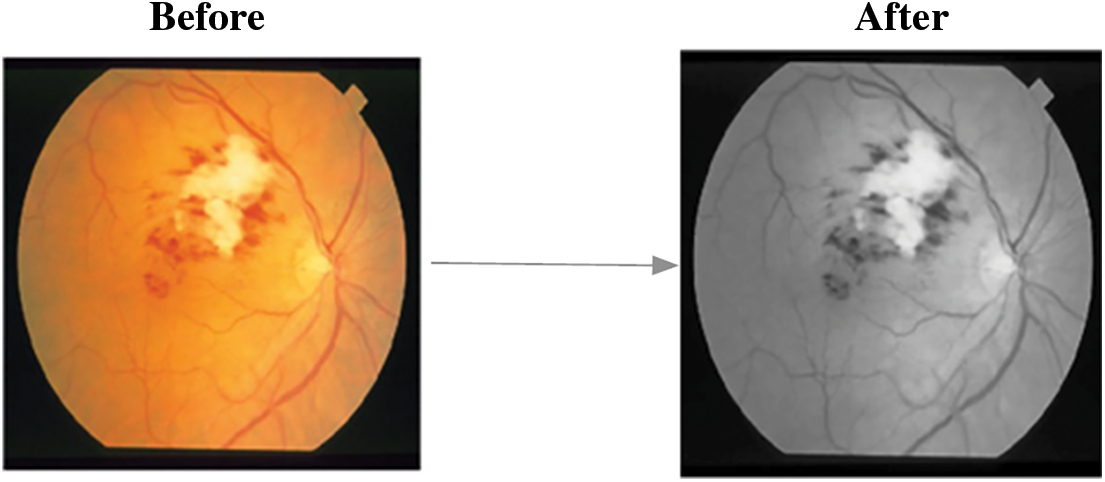

According to a recent World Health Organization (WHO) survey, India has the world's largest diabetic population, with 80% of diabetics susceptible to exudates and diabetic retinopathy. Exudates are commonly thought to be the first symptoms of Diabetic Retinopathy (DR). Exudates in the eyes are caused by protein and lipid leaking in the retina caused by damaged blood nerves. Fig. 1 depicts normal (A) and abnormal (B) retinal pictures, as well as exudates and diabetic retinopathy. Early diagnosis of exudates and DR can significantly lower the risk of blindness in diabetic individuals. A closer look at the retina is required for this, as is severe pupil dilation.

Figure 1: Retinal images (A). normal image and (B). abnormal image with DR and exudates

Fig. 4 depicts the corresponding findings after blood vessel elimination, and the steps for MCA-based object segmentation are detailed below.

Figure 4: A. FI with blood vessels B. FI without blood vessels

Based on the hard threshold rates, the process continues to obtain all ‘remi’ and the segmented object of the affected area from the fundus image is obtained. The corresponding sample figure is portrayed in Fig. 5.

Figure 5: A. Before segmentation B. After segmentation